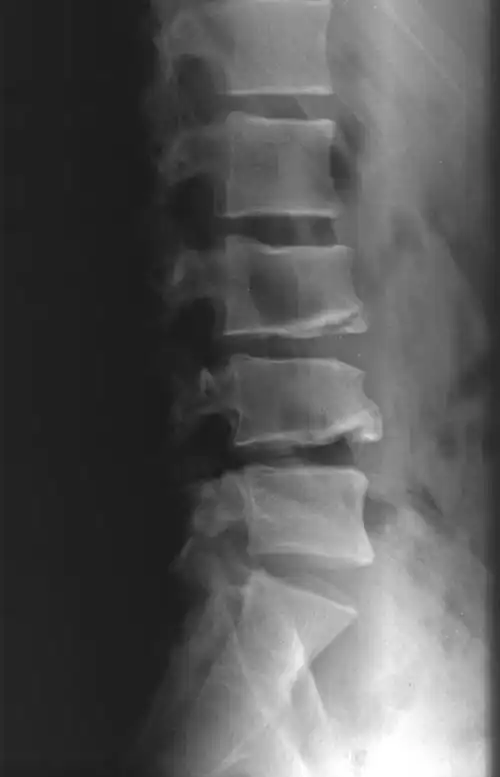

从这个片子看出l4l5腰椎间盘突出,突出量很大.

典型案例二:男,48岁,腰椎间盘突出.

腰椎间盘突出症

怎么看腰间盘突出的片子····片子上那个地方显示有问题?